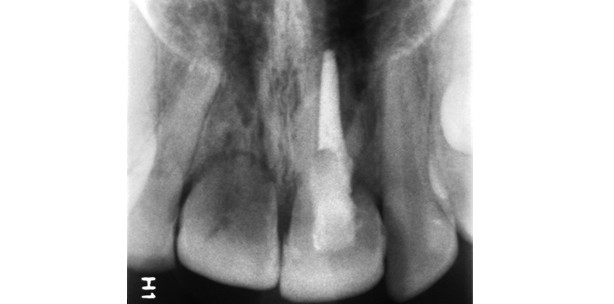

Weitere Indikationen zur Extraktion resultieren aus   Wurzelresorptionen (Abb. 2). Während die endo­dontisch bedingte Wurzel­resorption nach Desinfektion des Wurzelkanales zum Stillstand kommt, ist die sogenannte Ersatzresorption therapeutisch nicht beeinflussbar: An Orten, wo die ­Parodontalfibroblasten fehlen und der Alveolarknochen direkt Kontakt mit dem ­Zement hat, wird die Wurzel allmählich zu Knochen umgebaut und verschwindet mit der Zeit ganz. Die sogenannte zervikale Resorption beruht auf einer Infektion der Dentinkanälchen im schwer zugänglichen zervikalen Bereich der Wurzel. Sie kann durch eine dichte Füllung zum Stillstand ­gebracht werden, was jedoch nicht immer gelingt. Traumatisierte Zähne können auch auf Basis eines kieferorthopädischen Planes extrahiert werden. Sieht dieser unvermeidbare Extraktionen vor, so bietet sich an, schwer geschädigte Frontzähne zu entfernen und die gesunden Prämolaren in diesem Quadranten zu behalten. Unter Umständen kann eine solche Extraktion mit der Transplantation eines Prämolaren einhergehen. Schließlich kann es auch vorkommen, dass der finanzielle Spielraum für eine umfangreichere Behandlung fehlt. In diesem Fall ist zu entscheiden, ob man die Situation für eine spätere Sanierung „einfrieren“ kann (z.B. Wurzel endodontisch ­sichern, mittels Komposit überziehen und die Krone an einer Prothese ergänzen) oder ob es besser für den Patienten ist, zu extrahieren. Erfahrungsgemäß sind nur wenige Patienten von einer solchen Entscheidung betroffen.